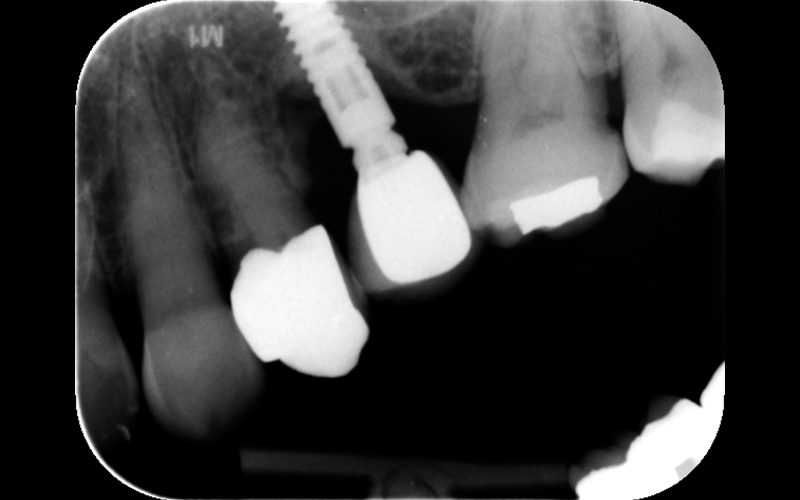

Nell'ultimo anno le è stata riscontrata complicanza a carico dei tessuti peri-implantari di elemento zona 25. L'esame visivo e lo status fotografico (Figs. 1-2) evidenziano un’alterazione dello stato dei tessuti molli peri-implantari, che guida il clinico verso un’indagine più approfondita tramite acquisizione RX. Si esegue perciò esame radiografico del sito coinvolto (Fig. 3), da cui risulta un’importante riassorbimento osseo a carico dell’impianto. Si procede con sondaggio peri-implantare profondo, con la finalità di definire estensione e forma del difetto (Fig. 4) e, associandolo all’esame radiografico, di eseguire la conta delle spire implantari esposte. Tale manovra verrà effettuata con l’impiego di anestetico da irrigazione, data la nota dolorolabilità in peri-implantite, in quanto tale patologia determina la perdita di barriere connettivali e pertanto la penetrazione in osso durante il sondaggio.

RX al baseline

Fig. 3 - Rx al baseline.